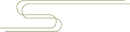

趾甲解剖